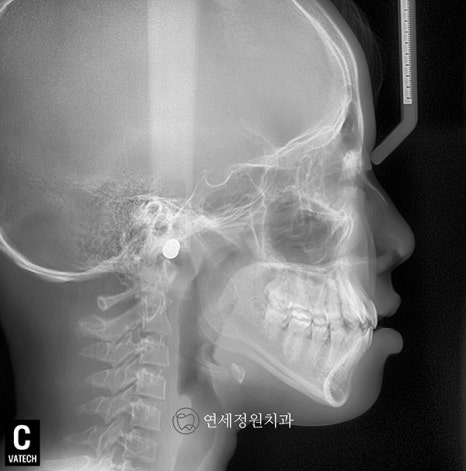

2019년 내원하였을 때 이미 유치는 다 빠지고 영구치가 다 올라온 상태였으며, 측면 엑스레이 상에서 전치부 교합은 좀더 안정적으로 잘 유지되고 있었습니다. 이제 영구치가 다 올라와서 2차교정을 시작해도 되는 시기였으나, 환자가 6개월 뒤 캐나다로 유학을 갈 예정이어서 교정 시작 시기는 환자분 스케줄에 맞춰서 시작하셔도 된다고 설명을 드렸습니다.

그리고 얼마 전 오랫만에 저희 연세정원치과로 환자분께서 찾아왔을 때는 이미 키가 거의 170cm가 다 된 숙녀가 되어있었습니다 :) (원래 악세서리는 다 제거하고 찍어야 하지만... 엑스레이 상에서도 여기저기 피어싱이 보이네요 ㅎㅎ) 방학이라 한국에 잠시 들른 동안 정기 검진을 받으러 왔는데, 위 앞니 하나가 틀어져 있고 입이 살짝 돌출이라 2차 교정 상담을 하셨으나, 한달 뒤 출국 일정 때문에 부분교정을 하기에도 시간은 부족한 상태였습니다.

2024년 7월

군입대를 하는 분들이나 외국 유학을 가는 환자들의 경우 종종 인비절라인을 추천드리고 있습니다. 인비절라인 투명교정의 경우 구강스캔한 자료를 바탕으로 클린체크라고 하는 치료 계획에 맞추어 단계별로 전체 장치가 제작되어 나오기 때문에 유학생의 경우에도 교정을 할 수 있다는 장점이 있습니다. 물론 정기적으로 내원하여 체크 받는 것이 가장 좋긴 하지만, 처음에 치료 계획을 잘 세우고 환자분도 장치를 열심히 잘 착용해준다면 내원하지 않고도 충분히 교정이 가능합니다.

이 환자분께서는 인비절라인으로 틀어진 앞니와 약간의 돌출감을 개선하기로 하였고, 한달 뒤 장치가 나오면 내원하여 어태치먼트도 붙이고 장치를 착용할 준비를 한 후 장치를 받아 출국하기로 하였습니다. 대략 1~1년 반 뒤에 귀국 예정이라 중간중간 사진을 찍어 보내주시면 중간 진행 상황을 확인을 해드리기로 했습니다. 인비절라인의 경우 교정이 잘 마무리되게 되면 외국에 계속 거주하시더라도 인비절라인의 비베라 유지장치를 캐나다로 배송해드릴 수 있다는 장점도 있습니다.